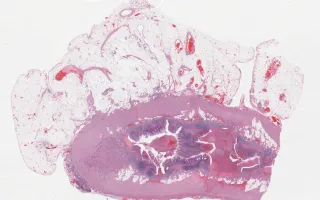

Appendix, goblet-cell carcinoid, H&E

Goblet-cell carcinoid of the appendix

Patient presented with acute appendicitis and perforation. An appendectomy was performed (this specimen), and the patient was followed. A subsequent recurrence of disease occurred (see Related Content).

Well-differentiated neuroendocrine tumours (“carcinoids”) of the appendix are usually found incidentally at appendectomy. When large or not confined to the tip, they can cause obstructive symptoms and/or appendicitis. Although uncommon, they account for a majority of appendiceal tumours. They are considered tumours of uncertain malignant potential. Goblet-cell carcinoid is a variant that shows both glandular and endocrine differentiation, with cells resembling normal intestinal goblet cells. Goblet-cell carcinoid is more aggressive than conventional carcinoids.

This appendiceal tumour was also stained for EMA (LMP99001) and Alcian Blue (LMP63103), highlighting the presence of epithelial differentiation and mucin production, respectively - see Related Content